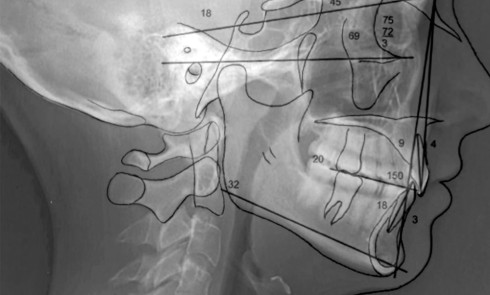

Article réservé à nos abonnés Distalisation maxillo-mandibulaire en technique linguale dans le cas d’une classe 1

Rubrique coordonnée par Kinz Bayet Présentation du cas Une patiente de 20 ans se présente en consultation pour réaliser un...